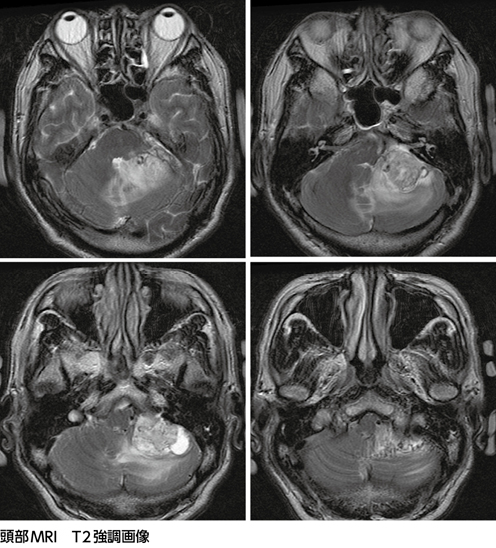

聴神経腫瘍・小脳橋角部腫瘍の手術とマネージメント | 河野 道宏。518T5bd0+FL._AC_SY200_QL15_.jpg。難聴で発見された左小脳橋角部腫瘍……聴神経腫瘍?[画像診断道場。・中古品を裁断しました。健康・医学 HUMAN BIOLOGY Sixteenth Edition。・・・・・・・・・・・・・・・・・・・・・・・・「聴神経腫瘍・小脳橋角部腫瘍の手術とマネージメント」定価: ¥ 19800#本。聴神経腫瘍・小脳橋角部腫瘍の手術とマネージメント | 河野 道宏。(「やや傷や汚れあり」にしております)・書き込みなし(見落としがあるかもしれませんが、ご了承ください)・DVDはついてませんが、シリアルコードが付いておりwebより問題なく動画視聴ができます。中古品であること、ご理解の上、ご購入ご検討ください。【裁断済】新OS NEXUS 下肢の骨折手術② 膝~足部

• 難聴で発見された左小脳橋角部腫瘍……聴神経腫瘍?[画像診断道場